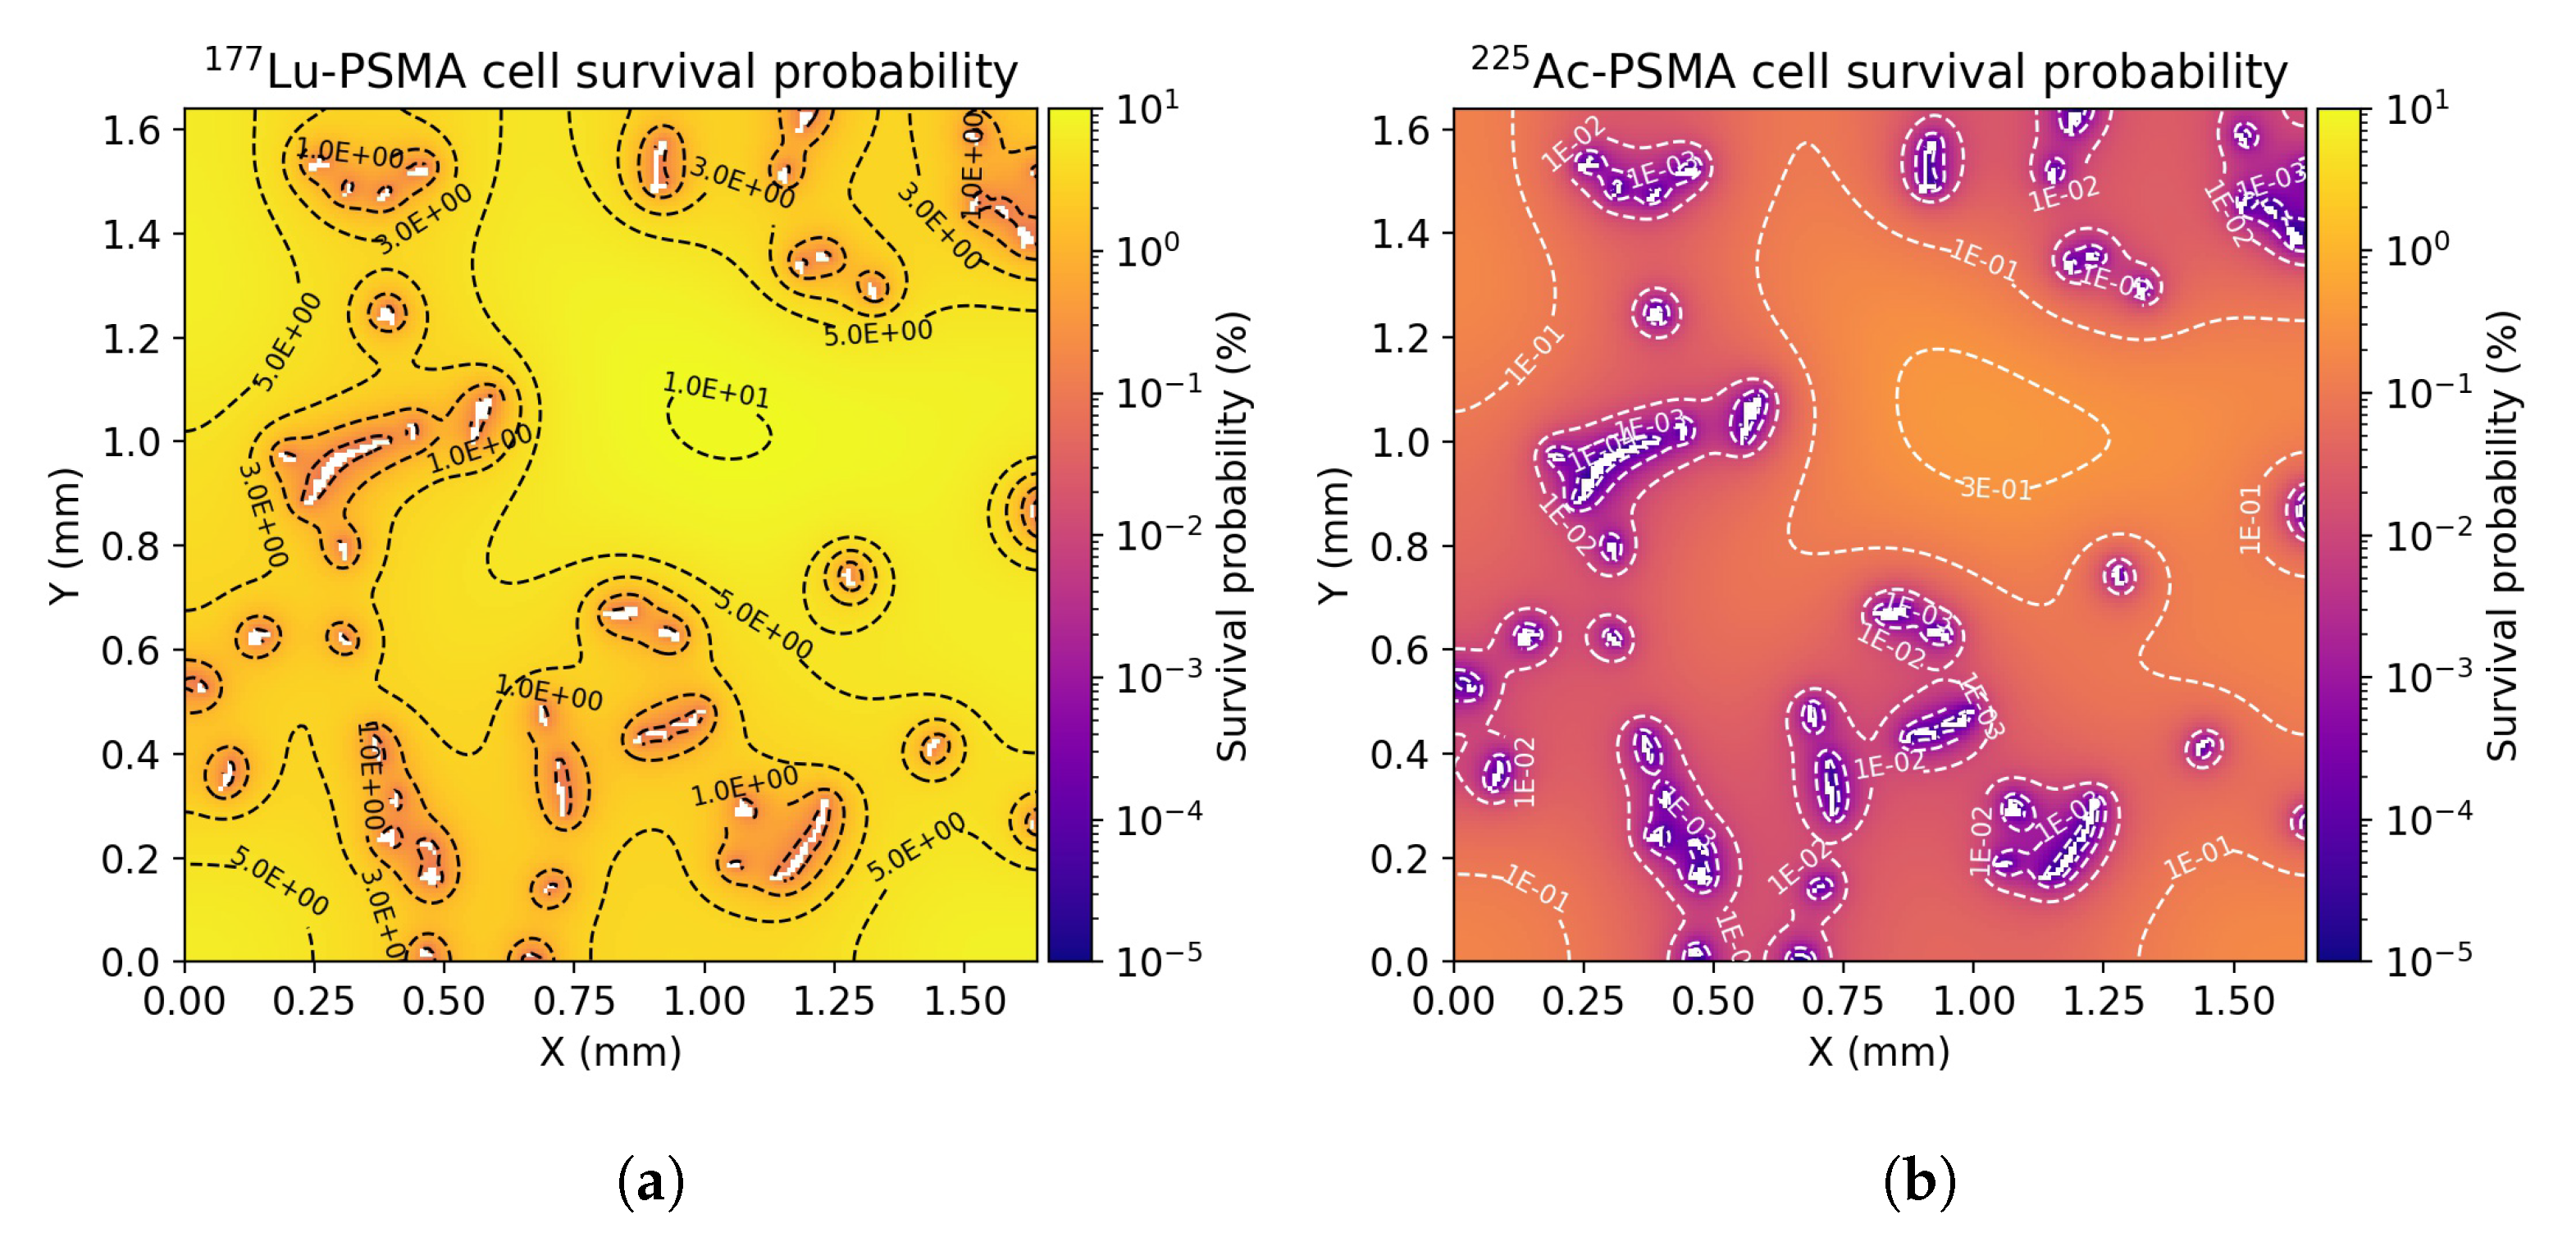

3.3. Radiobiological Efficacy Analysis